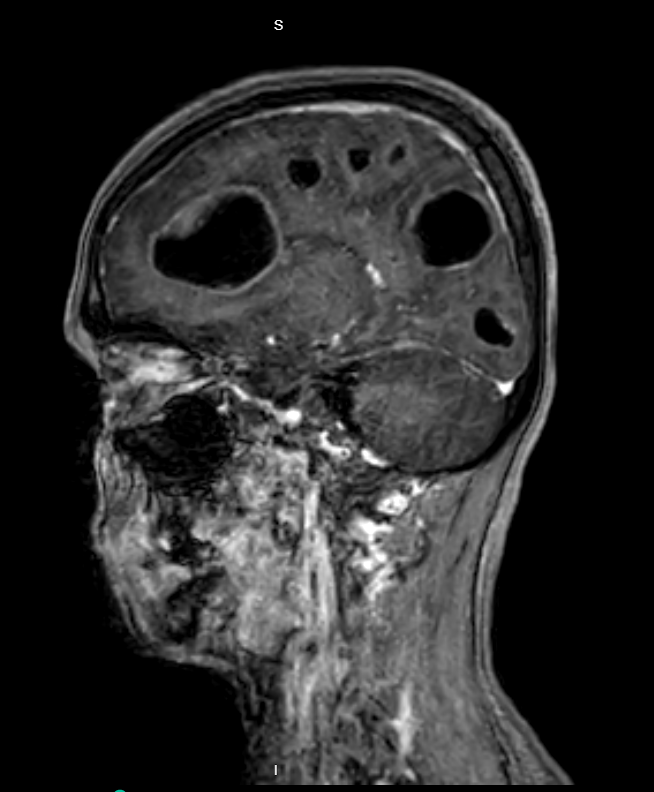

Case Presentation: A 40-year-old woman with a history of bipolar disorder and cannabis use disorder presented with four days of headache, dizziness, and vomiting. Initial examination revealed no focal neurological deficits except inconsistent orientation to time and cognitive slowing. She was treated symptomatically and planned for discharge. As she attempted to leave the ED, she was unable to ambulate due to unsteady gait.CT scan of the head and subsequent MRI showed multiple brain cysts, read as “suspicious for neurocysticercosis”. Dexamethasone and levetiracetam were started while antiparasitic treatment was deferred pending diagnostic confirmation and to reduce the risk of inflammatory complications. EEG was negative for seizure activity. Infectious work-up, including cysticercosis antibody, was negative. Chest x-ray showed no mass or infiltrate. By day three of hospitalization, the patient developed tangential speech, difficulty following commands, and worsened ataxia. CT scan of the chest revealed necrotic mediastinal lymph nodes. Endobronchial ultrasound (EBUS) showed an endobronchial lesion and multiple lymph nodes, which were biopsied. Histopathology confirmed small cell neuroendocrine carcinoma. The patient was diagnosed with small cell lung cancer (SCLC) with cystic brain metastases and subsequently received whole brain radiation and chemotherapy with etoposide/carboplatin.

IMAGE 1: MRI brain showing multiple cystic brain lesions